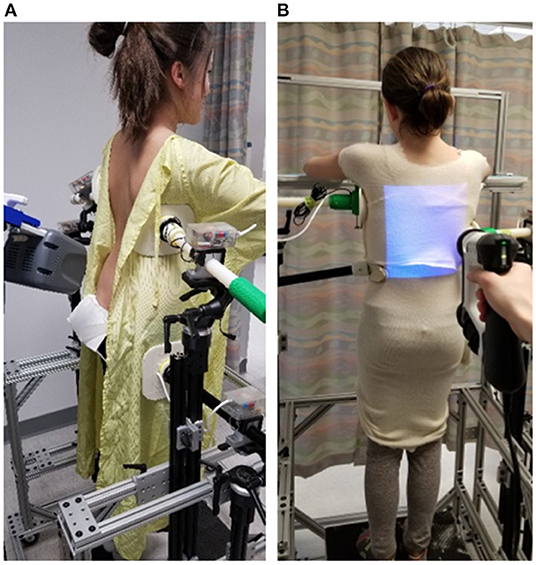

المسح ثلاثي الأبعاد لجسم المريض: حيث يتم عمل مسح كامل للجذع لتحديد مناطق الانحراف بدقة عالية، وهذا يسمح بتخطيط أكثر دقة من الطرق التقليدية.

إنشاء نموذج افتراضي متناظر: يُستخدم هذا النموذج لعكس صورة الجذع بحيث تمثل النسخة المثالية للجسم، مما يسهل مقارنة الشكل المثالي بالجسم الفعلي.

مقارنة الصورة الأصلية بالنموذج الافتراضي: تُستخدم الخرائط اللونية لتوضيح المناطق التي يتجاوز فيها الانحراف 6 ملم، وبالتالي تحديد نقاط الضغط داخل الحزام بدقة.

تخصيص الحزام حسب حاجة كل مريض: يتم تصميم وسائد الضغط بناءً على التحليل الثلاثي الأبعاد، لضمان توجيه القوى التصحيحية نحو مناطق الانحناء الحقيقية، بدلاً من الاعتماد على التقدير البصري فقط.

وبالتالي، يتم الجمع بين الدقة العلمية وراحة المراهق أثناء ارتداء الحزام، مما يحسن النتائج النهائية للعلاج.

نعم، فهي تعتمد على المسح الضوئي بدون أي تدخل، وتزيد من دقة تصميم الحزام .